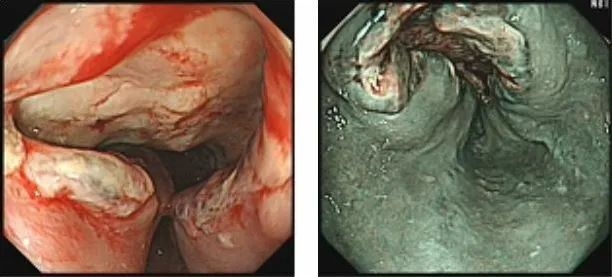

来到郑州大学五附院消化内科一病区后,胃镜检查提示"贲门癌",结合病理结果“贲门低分化腺癌”诊断明确,恶性程度高,预后差。消化内科一病区主任于泳立即组织胃癌MDT专家团队针对王伯伯的病情进行会诊讨论。